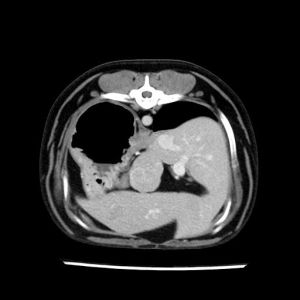

La lesione focale epatica , la ceus,la Tac e il chirurgo .